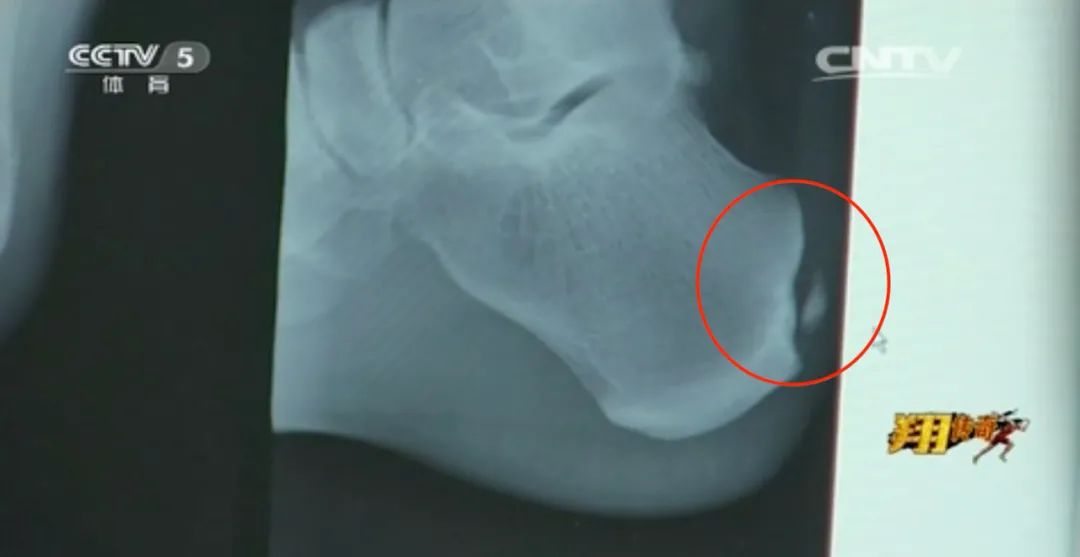

北京奧運賽前兩天,劉翔已被確診右腳跟腱炎,傷情被嚴格保密,不敢外泄。

上場前,醫生對劉翔進行非常規治療,即大力刺激痛處,以疼止疼。常人難以想象,純屬沒辦法的辦法。

檢錄前,劉翔狂踢硬海綿墊,試圖麻木自己的跟腱。

以防萬一,孫海平兜裏揣了三顆速效救心丸。

直到踏上賽道,劉翔依舊認為自己可以完成比賽,至少能拿前三。

結果第一槍有人搶跑,衝出去的劉翔才覺得一切都不對了,再走路只能一瘸一拐。

據好友所述,劉翔聊天時開玩笑講**“若是硬挺下來,跟腱徹底撕裂,有可能會去參加殘奧會。”**

病情比想象嚴重,跟腱鈣化,保守無用,只能開刀。最終取出三塊鈣化物質、一塊骨刺。

遭此手術,能不能繼續運動生涯還是個未知數。